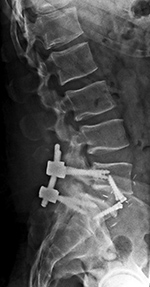

Lumbar spine bony disk strut, pedicle screws, and pedicle rods (AP view) |

Lumbar spine bony disk strut, pedicle screws, and pedicle rods (lateral view) |